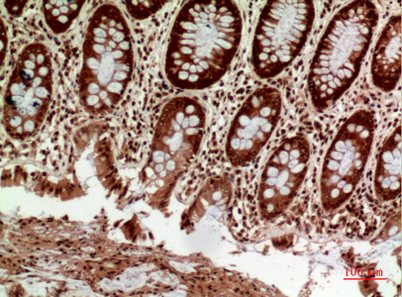

| Dilutions: | Western Blot: 1/500 - 1/2000. IHC-p: 1/100-1/300. ELISA: 1/20000. Not yet tested in other applications. |